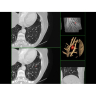

• Широкая область применения: от неврологии до кардиологии и онкологии.

Неврологические исследования

• Выявление инсультов, опухолей головного мозга и травматических повреждений.

• Диагностика заболеваний позвоночника и межпозвоночных грыж.